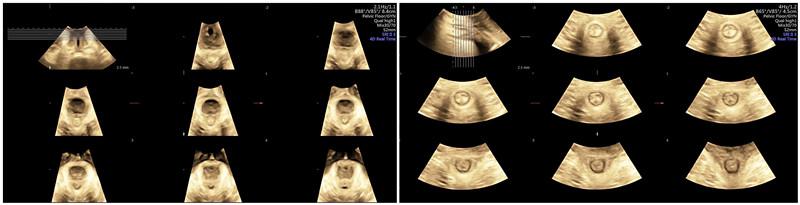

盆底超声以简便、实时、动态、无创等优点被国际妇产超声协会(ISUOG)和国际妇科泌尿学会 (IUGA)等推荐为首选的检查方法,今年初,中华医学会超声医学分会妇产超声学组已发布第一部《盆底超声中国专家共识》。

自2011年以来,在国家卫健委的支持下,中华预防医学会已在全国范围内开展中国妇女盆底功能障碍防治项目,旨在推广盆底疾病的筛查,我院超声医学科率先在全市开展盆底三维超声检查,为女性盆底健康保驾护航。

目前科室拥有GE Voluson E8超声诊断仪,具有实时动态三维/四维成像功能,可进行TUI超声断层成像和图像后处理,有专业盆底超声诊断医生2名,先后在武汉大学人民医院、中科大一附院、江苏省人民医院进修学习,并取得国际妇产超声协会(ISUOG)授权课程的培训证书。